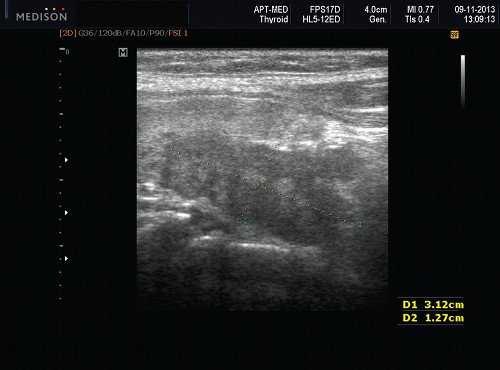

Доброкачественная смешанная опухоль подчелюстной железы при ультразвуковом исследовании

Общие особенности при ультразвуковом исследовании. Лучший диагностический признак: четко очерченная внутрижелезистая опухоль ПЧЖ, которая может выступать на ножке от края железы в поднижнечелюстное пространство (ПЧП), когда она становиться большой

Морфология. Малая плеоморфная аденома: одиночная, цельная, яйцевидная и хорошо разграниченная опухоль. Большая плеоморфная аденома на УЗИ: дольки ± кровоизлияние или некроз ± кальцификация

Результаты ультразвукового исследования слюнной железы

Серошкальное УЗИ. Хорошо выраженная, солидная и гипоэхогенная по сравнению с прилегающей тканью слюны. Однородная внутренняя эхо-структура с задним акустическим усилением. Опухоль имеет несколько тканевых границ и позволяет звуку легко проникать, вызывая улучшение заднего отдела. Большие опухоли могут иметь неоднородные внутренние эхосигналы из-за кровоизлияния и некроза. Гетерогенная плеоморфная аденома может иметь нечеткие границы, имитирующие злокачественную опухоль. Большие опухоли могут иметь дольки и появляться на ножке. Необычный кальциноз при ультразвуковом сканировании наблюдается при давней опухоли. Кожа и подкожные ткани в норме